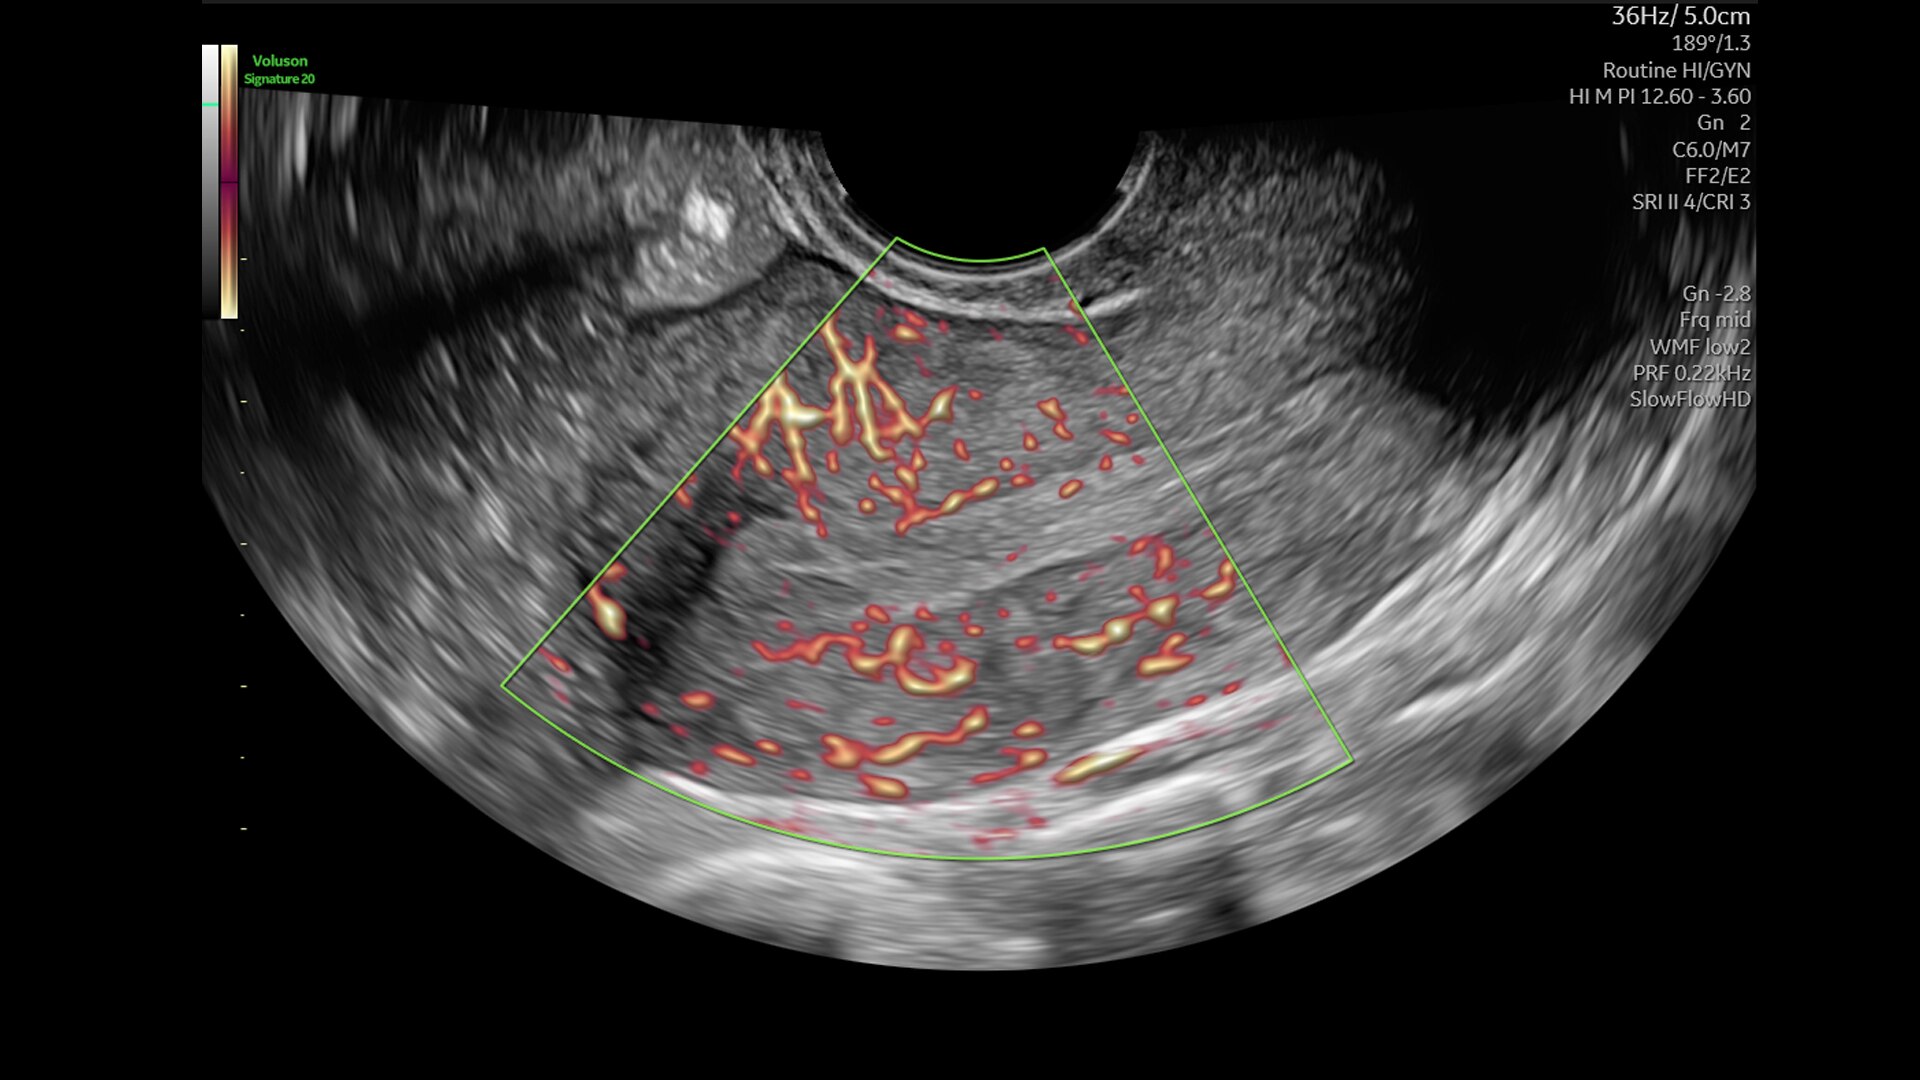

Visualize blood perfusion

Expand the range of visible blood flow to visualize blood perfusion in very small, low velocity vessels.

4-slowflowhd-clinical-image